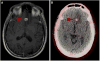

Methods: Five patients with known metastatic RCC were imaged with the low-molecular weight radiotracer ¹⁸F-DCFPyL, an inhibitor of the prostate-specific membrane antigen at 60 min post injection. ¹⁸F-DCFPyL PET/CT and conventional images (either contrast-enhanced computed tomography or magnetic resonance imaging) were centrally reviewed for suspected sites of disease.

Results: In all five patients imaged, sites of putative metastatic disease were readily identifiable by abnormal ¹⁸F-DCFPyL uptake, with overall more lesions detected than on conventional imaging. These PET-detected sites included lymph nodes, pancreatic parenchymal lesions, lung parenchymal lesions, a brain parenchymal lesion, and other soft tissue sites. ¹⁸F-DCFPyL uptake ranged from subtle to intense with maximum standardized uptake values (SUVmax) for the identified lesions of 1.6-19.3. Based upon this small patient series, limited pathology and imaging follow-up of these patients suggests a higher sensitivity for ¹⁸F-DCFPyL compared to conventional imaging in the detection of metastatic RCC (94.7 versus 78.9%).

Conclusions: PSMA expression in the tumor neovasculature of RCC has been previously established and is believed to provide the basis for the imaging findings presented here. PSMA-based PET/CT with radiotracers such as ¹⁸F-DCFPyL may allow more accurate staging of patients with RCC and conceivably the ability to predict and follow therapy in patients treated with agents targeting the neovasculature.